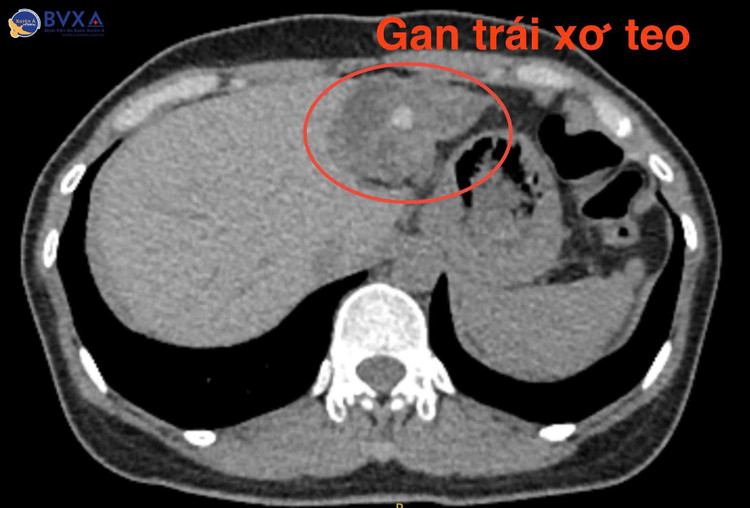

Bác sĩ cho biết: “Thám sát ổ bụng ê kíp phẫu thuật thấy ống mật chủ giãn với đường kính gần 11mm, gan trái teo một phần, đường mật gan trái giãn với đường kính 15mm có chứa nhiều sỏi. Trong quá trình mổ, ê-kíp phẫu thuật đã mở ống mật chủ để lấy ra nhiều viên sỏi nhỏ tụ lại thành cụm với kích thước 14x8mm, đồng thời cắt gan thùy trái và đặt dẫn lưu vào ống mật chủ”.

Bệnh phẩm lấy ra nhiều viên sỏi nhỏ tụ lại thành cụm với kích thước 14x8mm, đồng thời cắt gan thùy trái - Ảnh BVCC

Ca mổ được diễn ra trong gần 6 giờ đồng hồ, dưới sự dẫn dắt của TS.BS Lê Nguyên Khôi – chuyên gia Đơn vị gan – mật khoa Ngoại Tổng Quát hệ thống Bệnh viện Đa khoa Xuyên Á.

Các bác sĩ Khoa Ngoại Tổng Quát đã phẫu thuật lấy sỏi và cắt bỏ thùy trái gan chứa sỏi, kịp thời ngăn chặn nguy cơ viêm đường mật cấp, ung thư đường mật.